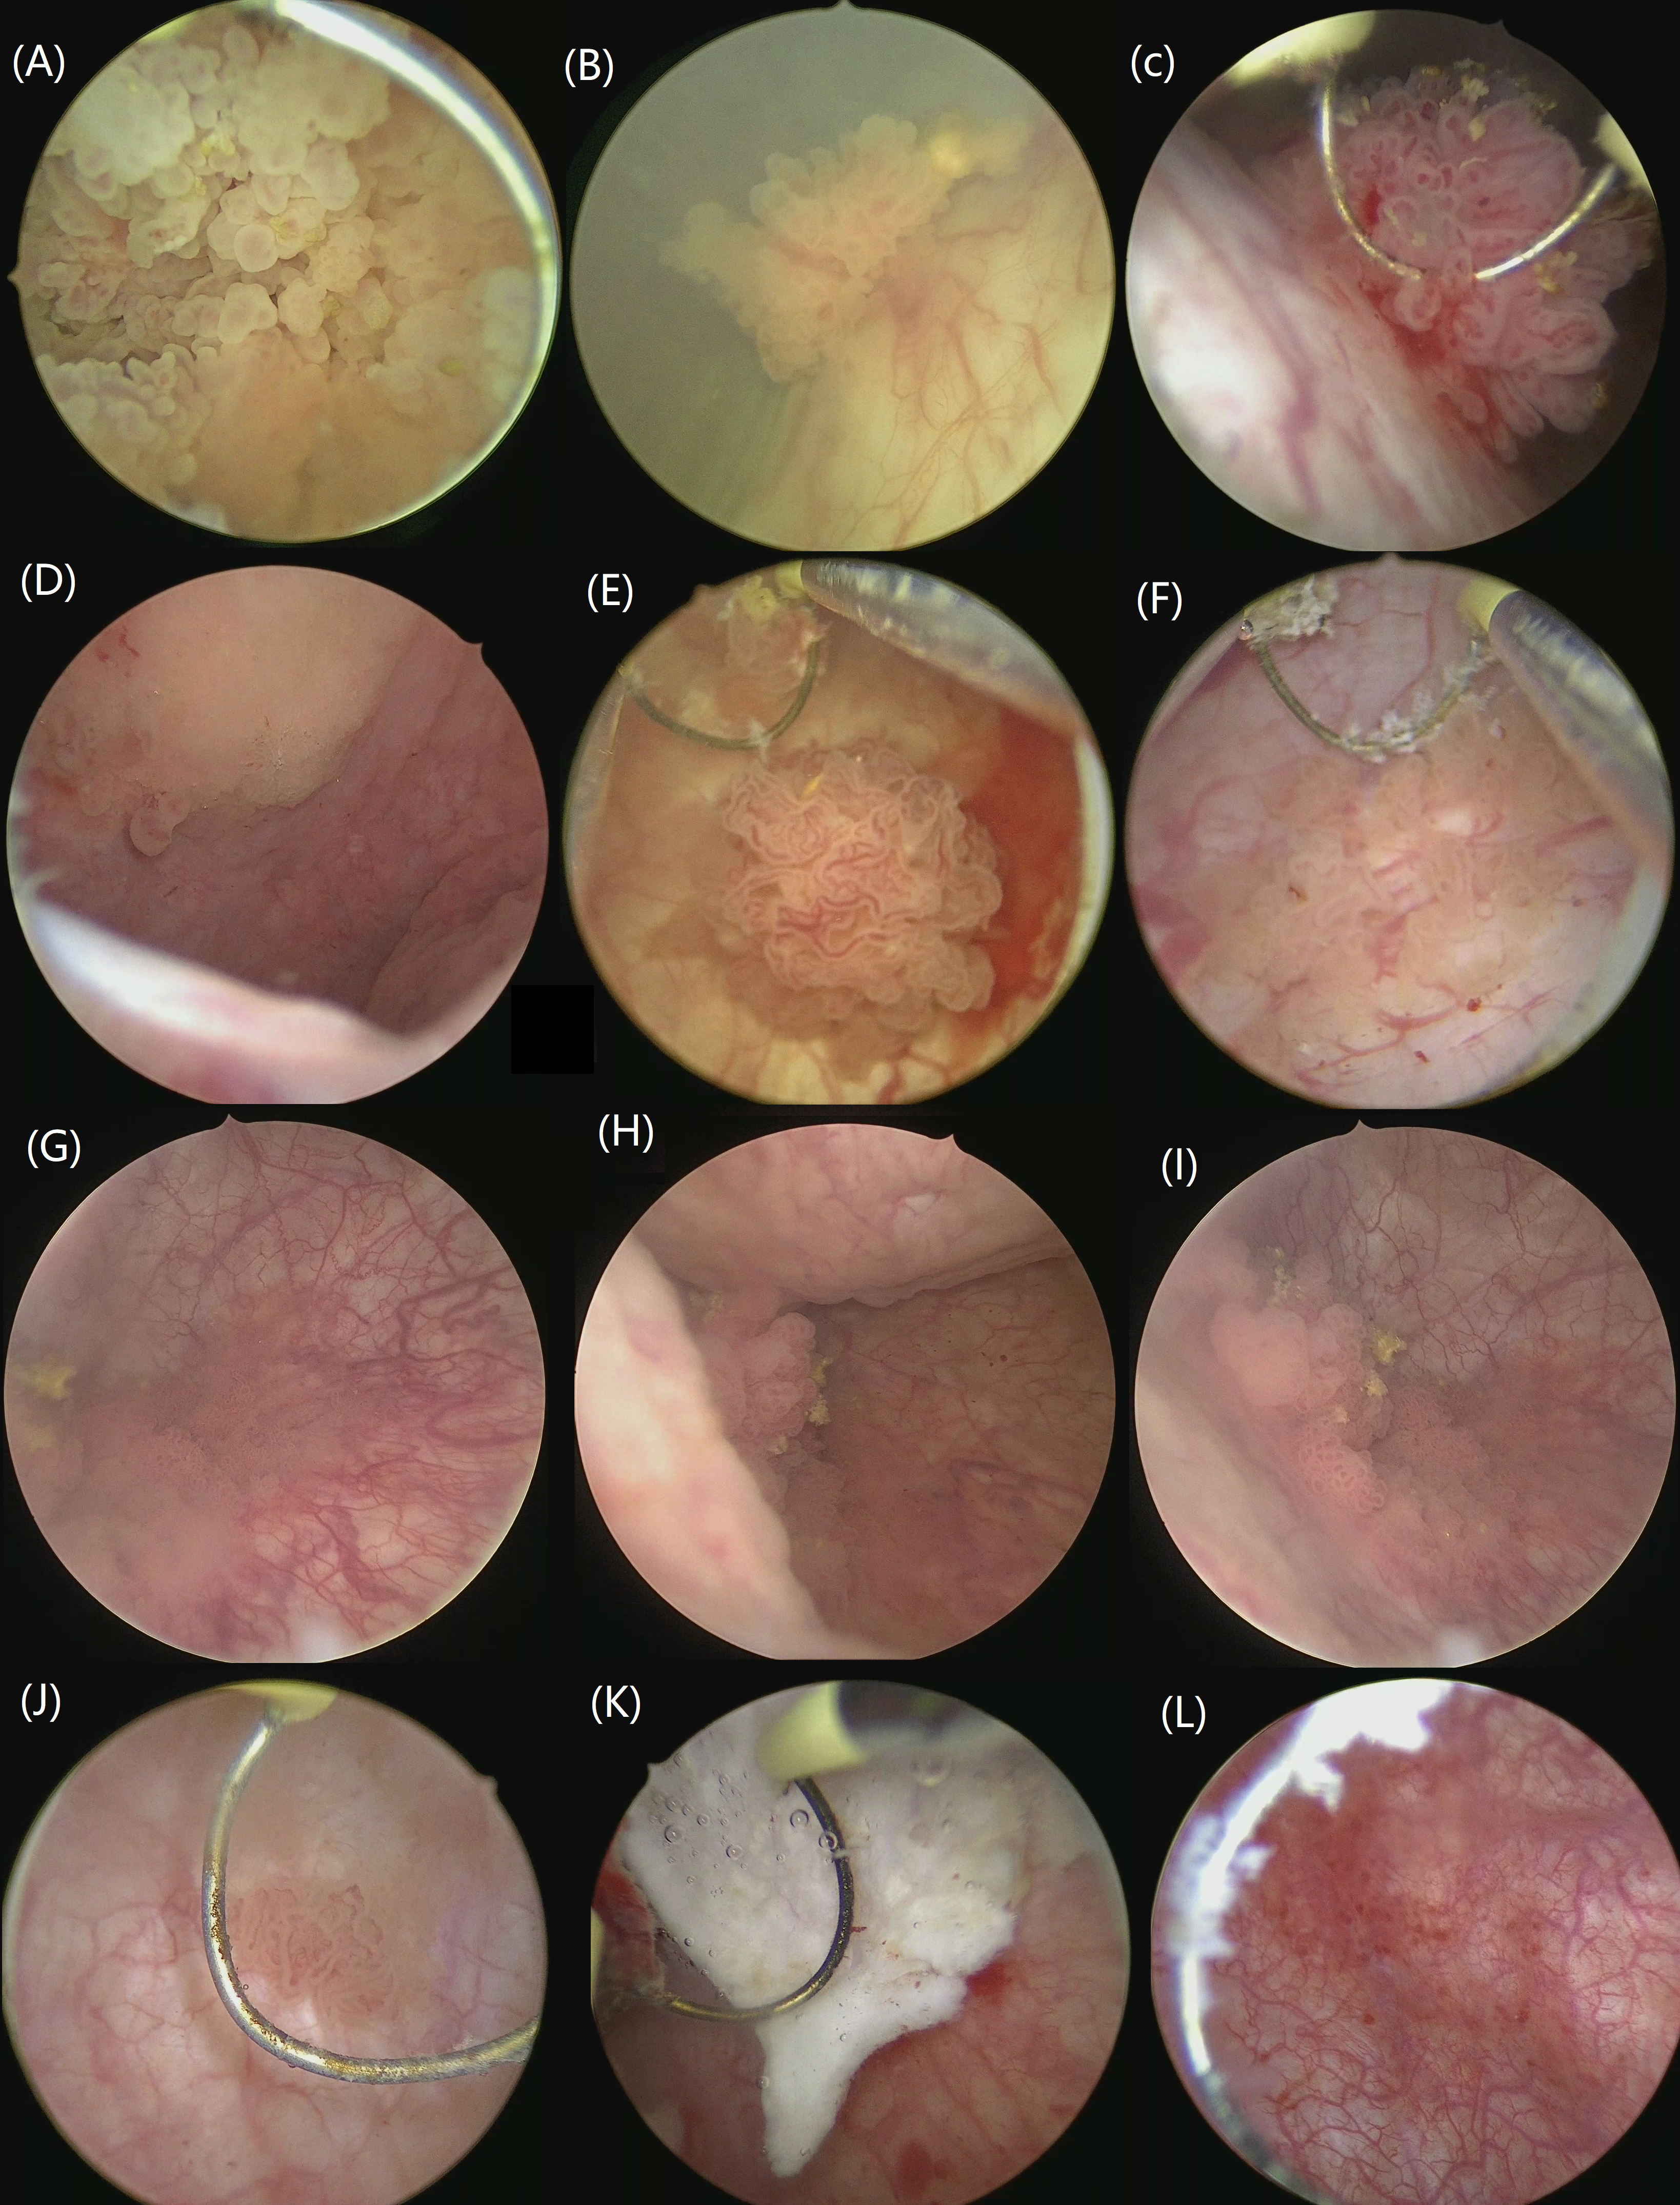

Refer to caption

Fig. 3: Cystoscopy data sample.

Fig. 3 displays dataset samples, showcasing the diversity in tumor appearances. For example, image (A) depicts a tumor that occupies the entire frame, demonstrating cases where the tumor is extensively spread. In contrast, (B) and (E), show tumors that are centered in the middle. Challenging cases are highlighted in images such as (G), where tumors borders are obscured by surrounding inflammation, making it difficult to distinguish its edges. This complexity is critical for training models to recognize and segment tumors accurately under varying conditions. Similarly, smaller tumors like (J), which blend seamlessly into the background or nestle in the bladder’s corners as seen in (H), represent another challenge due to their subtle presentation. Additionally, the dataset includes images of cystites, such as the one shown in (K), where the inflammation’s distinct appearance provides a contrast to tumor images. Image (L) further demonstrates an inflamed area, adding to the dataset’s comprehensiveness by including various pathological presentations within the bladder.